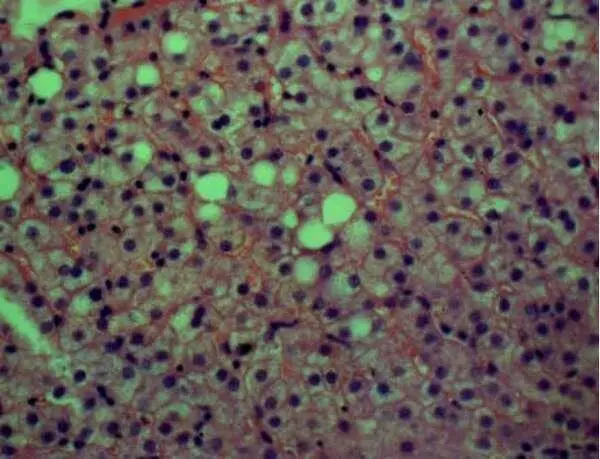

Рисунок 11 – Слабо выраженный перисинусоидальный фиброз («капилляризация» синусоидов); жировая и белковая дистрофия гепатоцитов. Окраска гематоксилином и эозином, Х100